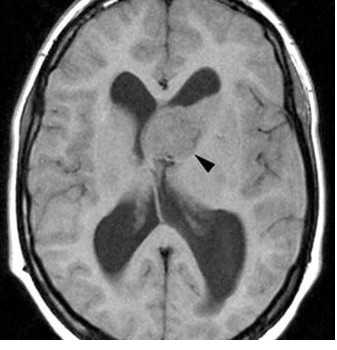

(а) МРТ, Т1-ВИ, аксиальный срез: у мальчика 13 лет с ТС по ходу переднего рога правого бокового желудочка определяются 2 СЭУ.

Кроме того, в переднем роге левого бокового желудочка, прилегая к отверстию Монро, визуализируется двудольчатое объемное образование со смешанной интенсивностью сигнала.

Обратите внимание на кортикальные туберсы, нечеткость границ между серым и белым веществом.

(б) MPT, Т1 -ВИ, более краниальный аксиальный срез: у того же пациента определяются другие СЭУ.

(а) МРТ, постконтрастное T1BИ, режим подавления сигнала от жира: у того же пациента определяется контрастирование СЭУ в области переднего рога правого бокового желудочка, а также контрастирование образования дольчатой структуры в области переднего рога левого бокового желудочка.

Зоны гиперинтесивного сигнала в форме «языков пламени» в структуре БВ на данном изображении видны лучше. Визуализируется один радиальный пучок, простирающийся до границы бокового желудочка.

(б) МРТ, постконтрастное Т1-ВИ, сагиттальный срез: у того же пациента образование левого переднего рога с дольчатой структурой напрямую прилежит к отверстию Монро, но не обтурирует его.

Предполагаемая СГКА у данного пациента наблюдается без хирургического вмешательства и остается стабильной уже в течение нескольких лет.